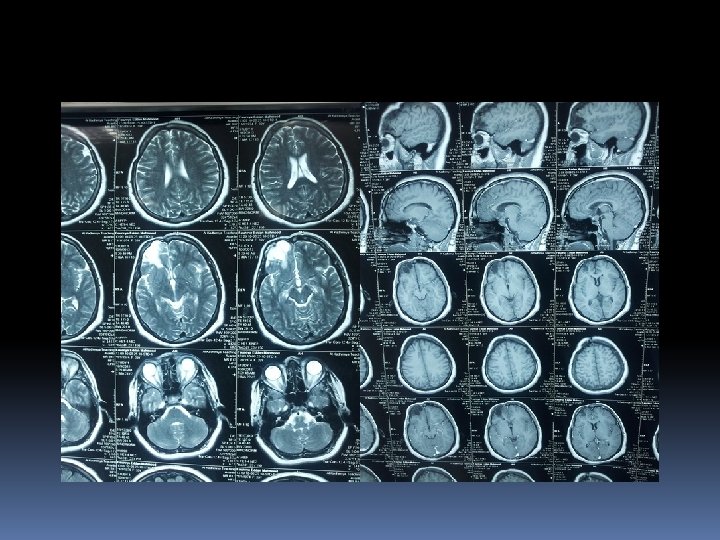

Neuroimaging studies C. T SCAN of sella with thin slices(1. 5 -2 mm)plus contrast , to exclude ac. Haemorrhage. MRI of sellar & parasellar(<2. 5 mm slices) Cerebral angiography or MRI angio to exclude aneurysms.

Pre.

Post

Post medical.